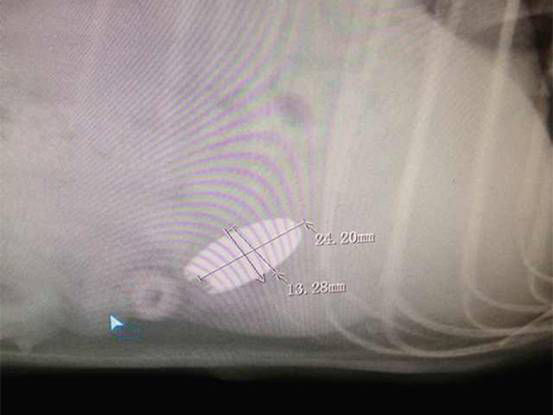

主诉:该犬自小有咬食杂物的恶习,3天前啃咬一枚硬币后不慎整个吞下,一直未见排出且精神日渐沉郁,食欲废绝并伴随不时呕吐。呕吐物为黄色透明状胃液。医生根据主人提供的信息排除传染病的可能性,立即着手拍摄X光片,DR显示该犬胃内有高密度异物。考虑到长时间呕吐情况,自行排出异物的可能性不大,医生切合实际与主人商议,该犬主人同意实施胃切开手术。

图2:DR诊断侧位照